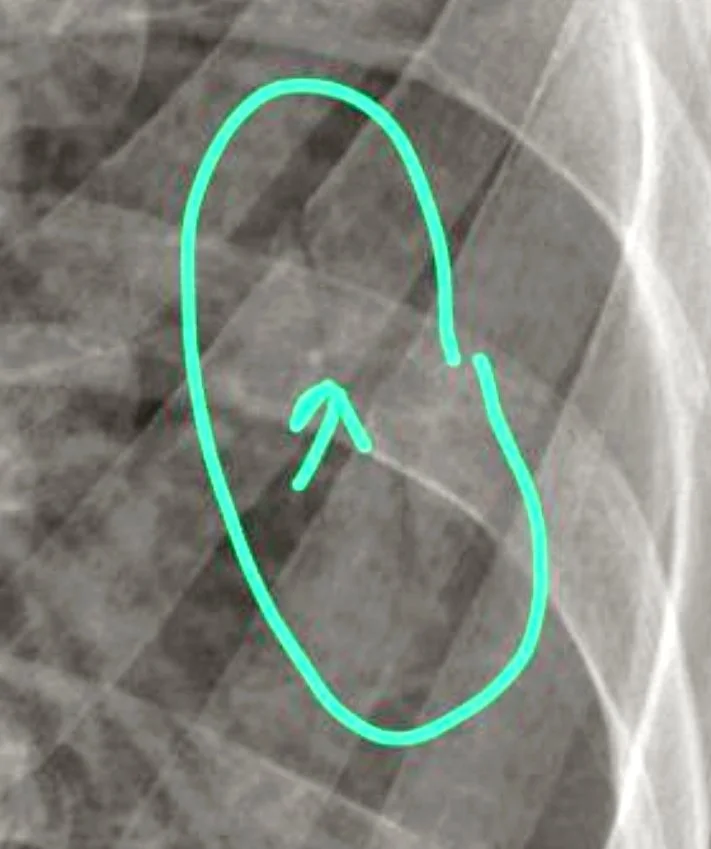

• Radiographies : passées à trois reprises afin de suivre l'évolution, je ne rencontre personne, et le compte rendu m’est envoyé par mail :

- Fracture non déplacée de la jonction des arcs moyens et antérieurs de K6 et K7 à gauche.

En clair, deux côtes qui ne se touchent plus, mais non déplacées, fracturées dans le virage (l’arc), ce que l’on appelle les vraies côtes, attachées à l’arrière et à l’avant par le sternum (d’ailleurs la douleur va s'avérer plus intense aux attaches qu’à la fracture même).

• Kinésithérapeute : Ne trouvant aucun médecin disponible rapidement pour m’ausculter et analyser mes radios, c’est par les réseaux sociaux que j’obtiens conseil auprès de deux kinés (c’est par eux que j’ai pu visualiser les fractures sur les radios). Je fais également une consultation en présentiel, mais sans aucun soulagement et de mauvais conseils.